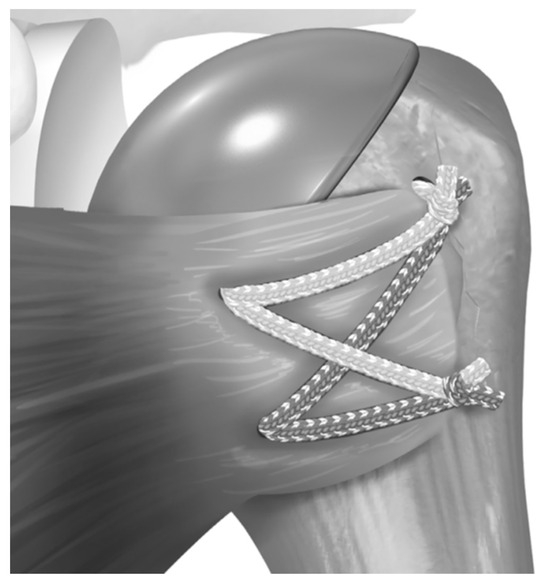

2.2. Surgical Procedure